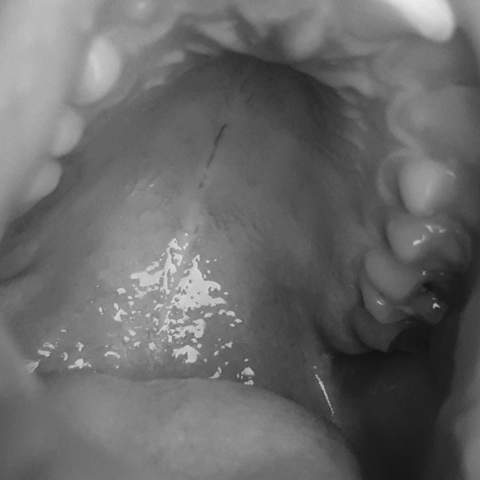

41+ Pickel Im Oberen Mundraum PNG. Pickel am mund oder rund um den mund treten relativ häufig auf. Es kann allerdings auch passieren, dass pickel im mund entstehen.

Pickel im gesicht haben eine bedeutung. Zum glück ist es unkompliziert, sie wieder loszuwerden. Seid ein paar tagen habe ich einen eitrigen pickel bzw mittlerweile schon zwei (abzess) im inneren meiner linken backe höhe letzter backenzahn!

Tumoren im mundraum sind die siebthäufigste krebserkrankung in deutschland.